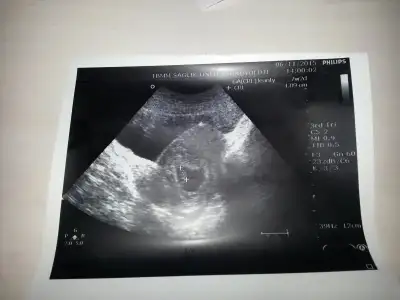

Buda son iki foto kizlar tahmininizi bekliyorum

Eklentiler

• 20151128_093323.webp

20151128_093323.webp

18,3 KB · Görüntüleme: 85

• 20151128_093331.webp

20151128_093331.webp

12,9 KB · Görüntüleme: 80